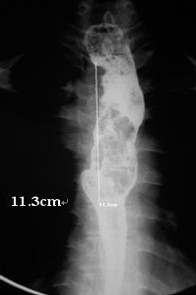

女,51歲,以“進(jìn)行性吞咽困難1年”為主訴于2007年2月19日入院。鋇餐造影、胃鏡示食管上段占位性病變,確診為食道鱗癌(圖1),拒絕手術(shù),行放療+今又生治療。食道鏡下瘤內(nèi)注射今又生,1×1012VP/次/周×6,放療在今又生注射3 d后開始,采用常規(guī)分割三野等中心照射,劑量65cGY。治療結(jié)束后4周,食管X線、胸部CT顯示腫瘤完全消退(圖4-5)。

治療前